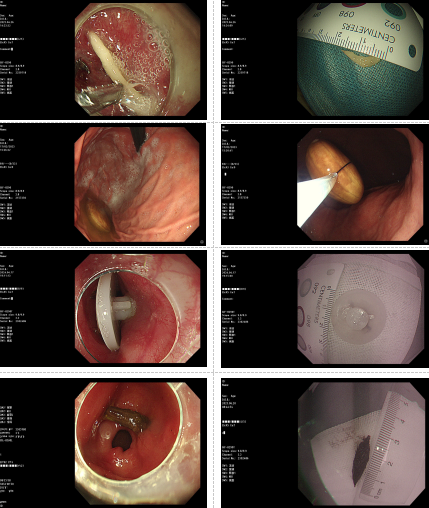

临沂市中医医院高铁院区内镜中心:消化道异物,正确处理是关键

不慎吞异物,莫要慌与怕;内镜巧取出,安全又高效。临沂市中医医院高铁院区内镜中心为您保驾护航!

10月7日,内镜专家到临沂市中医医院坐诊

临沂市中医医院成立同济大学附属东方医院消化内镜中心徐美东教授工作站,定期邀请同济大学附属东方医院消化内镜中心徐美东教授团队来院精查手术,让临沂百姓在家门口享受到国内一流专家的诊疗服务,尤其是疑难、复杂